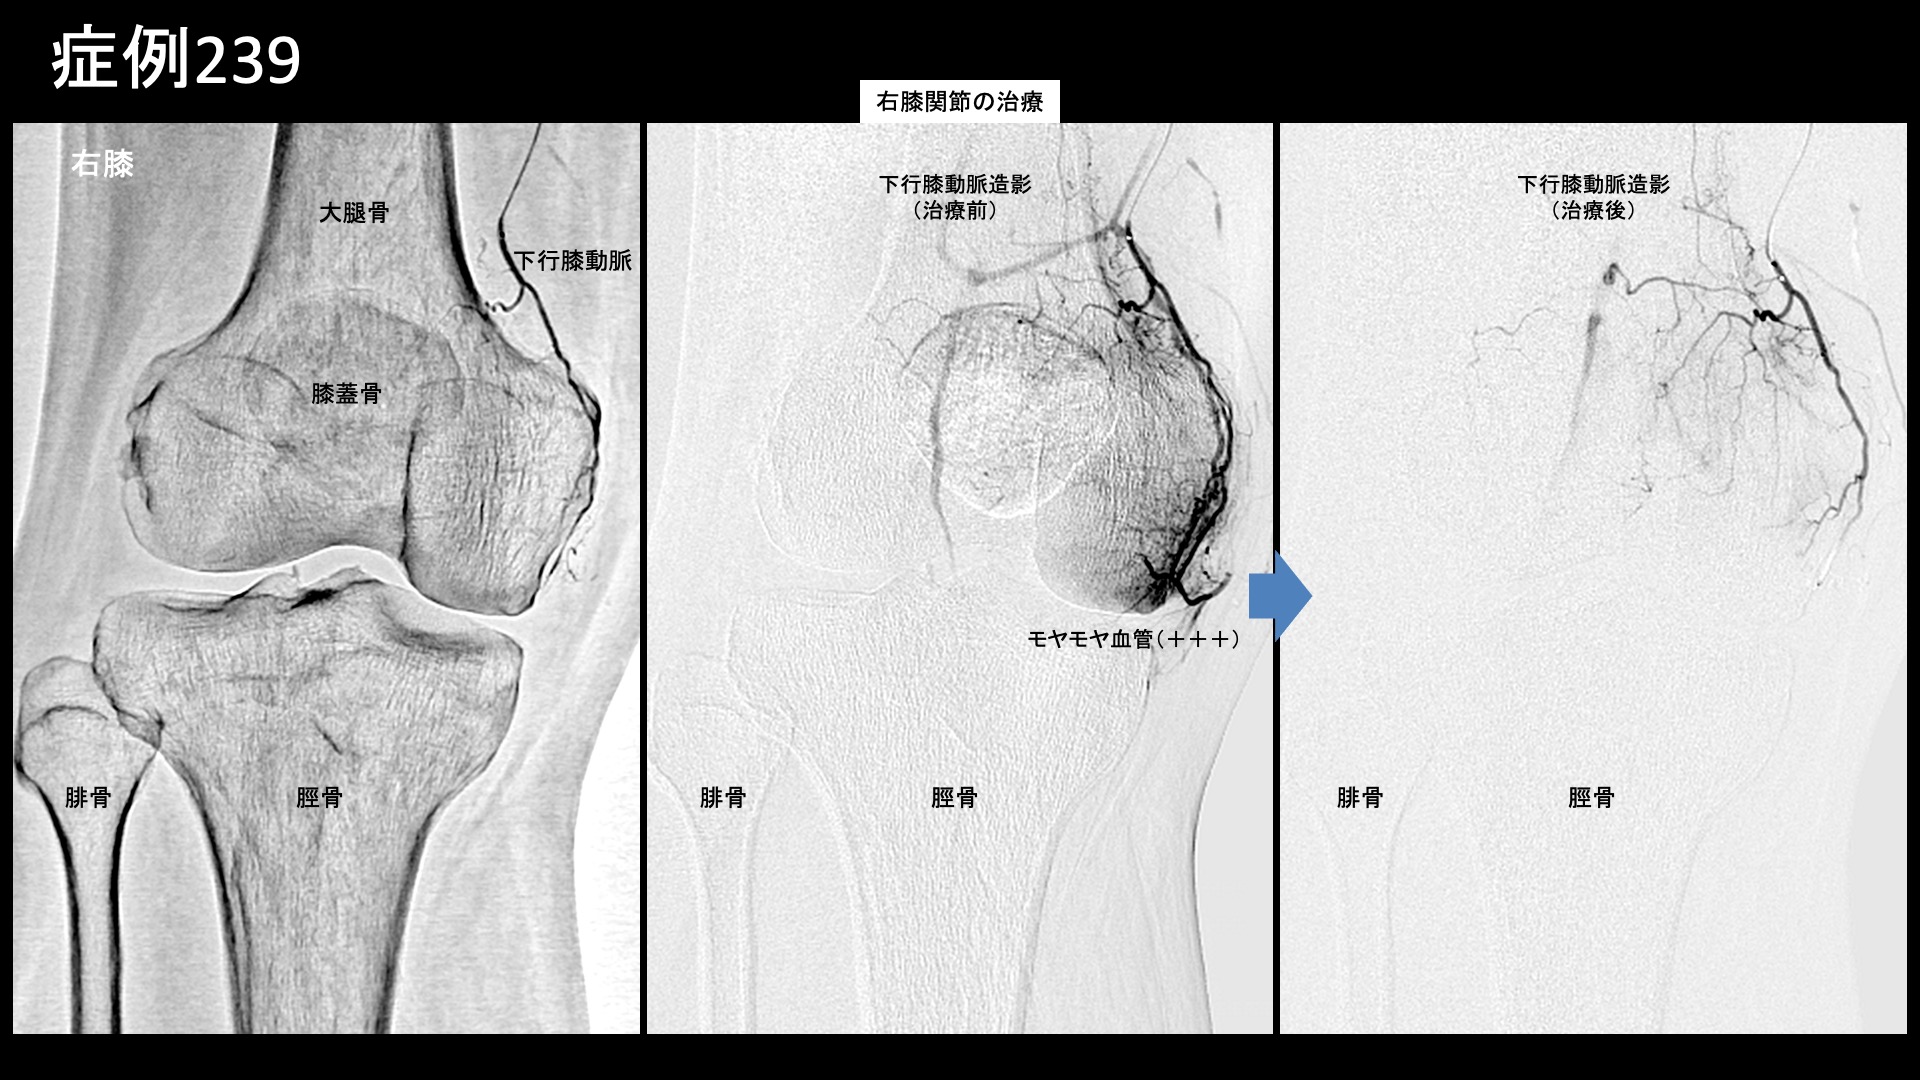

膝:変形性膝関節症など 【70代:男性】夜間痛がその日のうちに改善!強い炎症を伴った変形性膝関節症に対する運動器カテーテル治療(変形性膝関節症) 2025.09.23 鴨井院長による動画解説 受診までの経過 半年前から右膝が痛むようになりました。夜間に疼くようにもなったため、当院を受診しました。 診察時の所見 レントゲンでは両膝関節に中等度以下の変形が見られました(KL分類2/4程度)。両足は扁平足でした。エコーでも同様に中等度までの変形にとどまっていましたが、一方で、異常血流信号は非常に旺盛にみられ、強い炎症が示唆されました。 良い治療適応と判断し、モヤモヤ血管(病的新生血管)に対する運動器カテーテル治療(微細動脈塞栓術)を受けていただきました。 治療の所見 血管造影を行うと、左右とも全周性にモヤモヤ血管が濃染像として描出されました(写真は、下行膝動脈、内側下膝動脈、外側下膝動脈の各血管造影について掲載)。やはり、強い炎症を反映した所見でした。治療後は画像上速やかに消失しました。 治療後の経過 治療直後から症状が改善し、ほぼ痛みが無くなりました。帰り道にも既に違いを実感し、その日の夜にはいつもじんじんと疼いていた痛みが無くなっていました。治療後1ヶ月の再診時には、奇跡的に良くなっている、こんなにも良くなるものかと驚かれました。これまでと人生観が変わり、何か新しいことを初めてみようかと思えるようになったと言われました。その後も違和感を生じることはあるものの、痛みが再燃することはありませんでした。治療後3ヶ月でも順調に経過されており、終診としました。 通常の変形性膝関節症ではもう少し時間をかけて改善することが多いのですが、非常に早期から改善しました。モヤモヤ血管(病的新生血管)に対する運動器カテーテル治療(微細動脈塞栓術)は、炎症が強いほど早期から改善が得られる傾向がありますが、まさにそうした症例でした(夜間痛も強い炎症を反映した臨床所見の一つです)。まだ変形が高度に進行していない内に治療を受けていただけたことも、良い結果が得られた要因です。カテーテル治療の強みを最大限に生かすためには、高度の変形にまで進行する前にご検討いただくとよいと思います。 膝の痛みについては、何とか歩けるうちは医療機関を受診しないという方も多く、受診を決断した時には既に変形が高度に進行していたということも少なくありません。変形性関節症は進行性の病気であり、加齢によっても進行しますが、進行するほど種々の治療が効きにくくなってしまいます。ある程度までの状態でしっかりと治し、その後の進行を予防するための靴・インソール調整、筋力トレーニングなどに取り組み、日常生活についても指導を受けた方が、結果的には長く自分の足で健康に歩くことができますので早めに対処していただくことをおすすめします。昨今では、レントゲンに加えてMRI検査まで受けずともエコー検査である程度の詳細な状態を把握することができますし、そうした医療機関が増えてきています。エコー検査は気軽に受けられますので、状態に応じて、時々チェックを受けるのも良いと思います。 変形性膝関節症の詳しい病状説明はこちら 【80代:女性】新型コロナウイルス感染を契機に悪化した変形性腰椎症による腰痛/坐骨神経痛(新型コロナウイルス感染、変形性腰椎症、腰痛、坐骨神経痛) 前の記事 【10代:男性】恥骨が痛くて走れない、スポーツが原因で生じた恥骨結合炎に対するモヤモヤ血管治療(恥骨結合炎) 次の記事